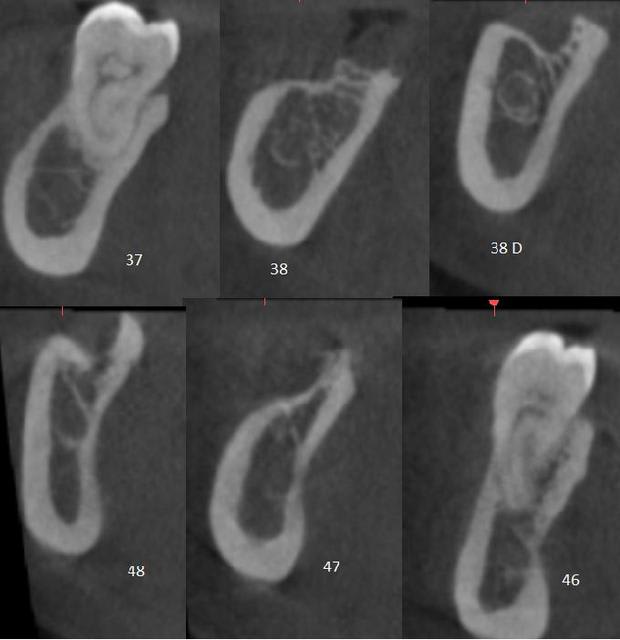

Marc pour avoir eu les fichiers dicom et le modèle "en vrai" dans les mains, c'est très très fin et très très dense

je pense sincèrement que les options d'augmentations sont plus sages...et perso, j'ai ma préférence pour un bloc usiné chez biobank...juste à ouvrir (après ostéotension, là on est tous d'accord là dessus...) et ostéosynthèser, une membrane pour protéger et zou